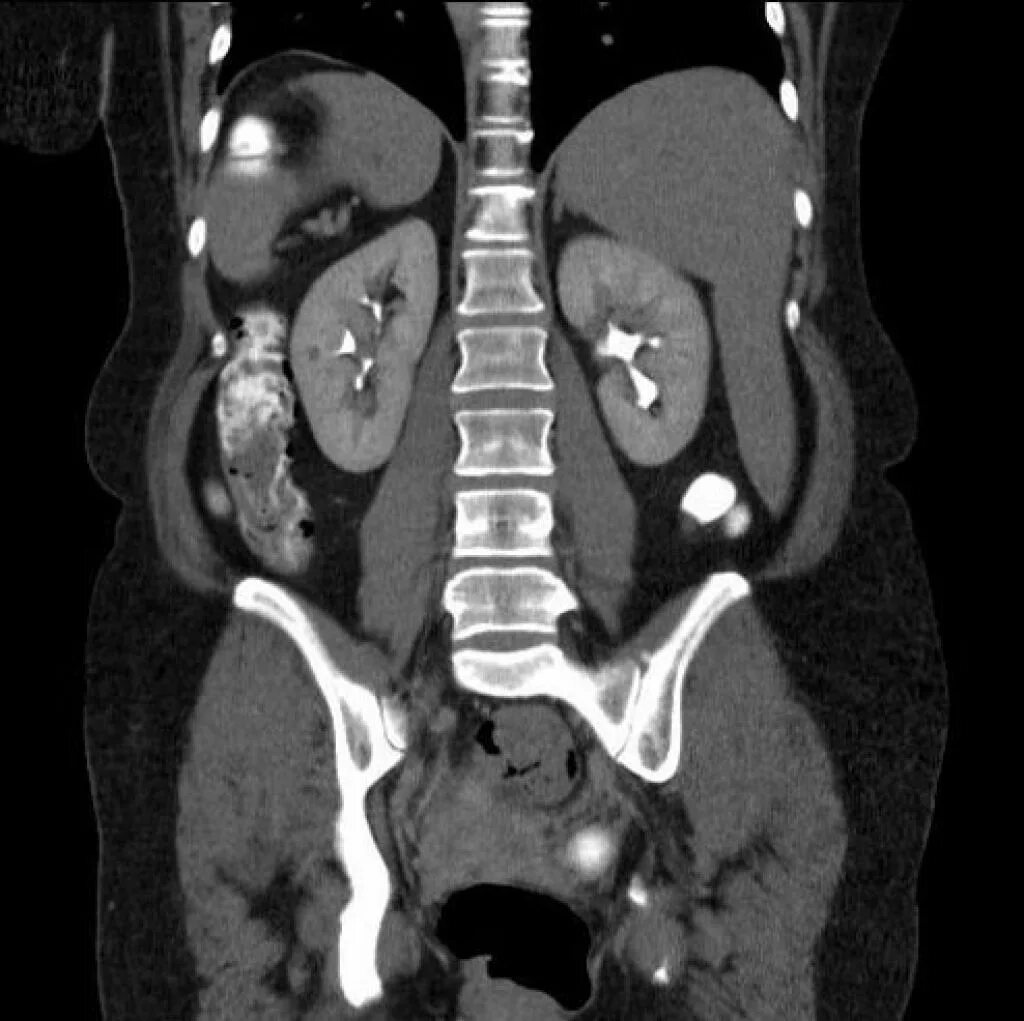

Мрт обп с контрастированием